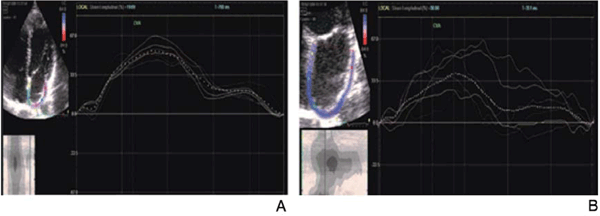

Figura 1: A) Ilustración del registro de strain auricular obtenido a partir de una vista de 4 cámaras sin zoom. A la izquierda se observa el seguimiento parietal por parte del software sobre la pared auricular de acuerdo con la etapa del ciclo cardíaco. A la derecha se observa el registro de strain auricular. Cada línea de color representa la deformación de cada sector de la pared auricular. La línea punteada refleja la deformación global de la aurícula acorde a la etapa del ciclo cardíaco. B) A la izquierda se observa el seguimiento parietal (trazado azul) del movimiento auricular de acuerdo con la etapa del ciclo cardíaco. A la derecha se ilustra el registro de strain auricular, obsérvese el constante movimiento ondulante y asincrónico de todas sus paredes.

Se desaconseja la adquisición de imágenes auriculares con zoom. Nuestra experiencia de trabajo nos ha mostrado escaso seguimiento de la excursión parietal auricular por el software y adquisición de malos trazados de strain cuando se adquieren con zoom (Figura 1B).